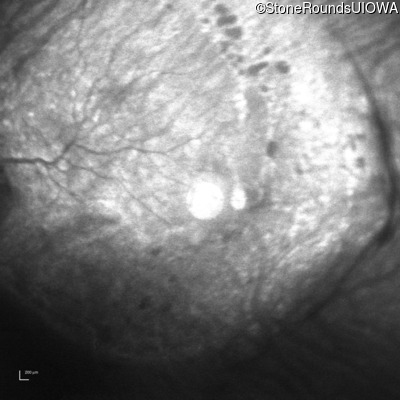

Infrared Fundus Photograph - Right - 10/200

Exemplar